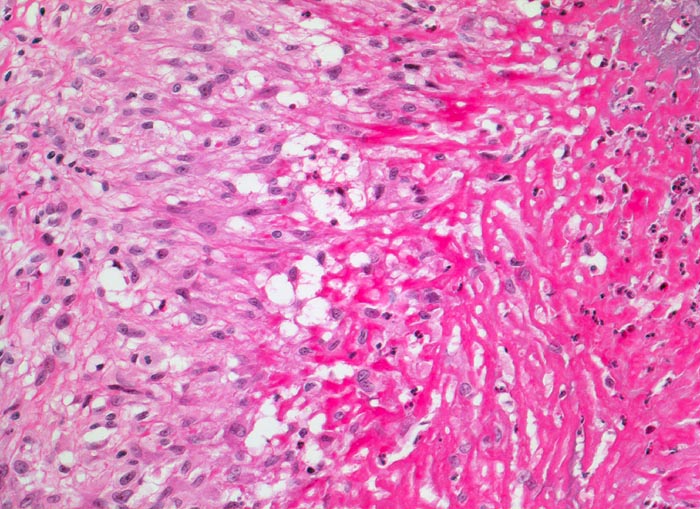

PathoPic – image database / PathoPic ID 3533 - Rheumatismus nodosus

Rheumatismus nodosus

Systemerkrankung/Immunpathologie

Weichteile Arm

Rechts im Bild hypereosinophile fibrinoide Nekrose mit Einschluss von neutrophilen Granulozyten. Angrenzend an die fibrinoide Nekrose links im Bild palisadenförmig angeordnete Epitheloidzellen. Etwas weiter aussen sind locker eingestreute Lymphozyten und Granulozyten zwischen den Epitheloidzellen erkennbar.

Patientin mit rheumatoider Arthritis. Derber, verschieblicher subkutaner Knoten an der Streckseite des Unterarmes nahe des Ellenbogens.

Histologie

200